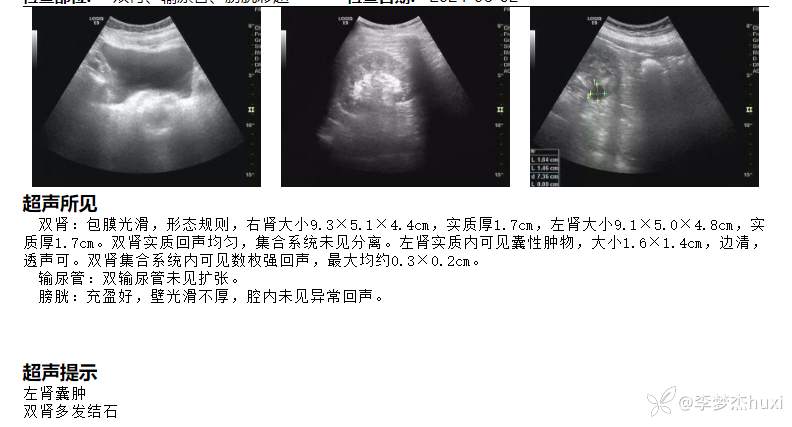

4.辅助检查:待回报。